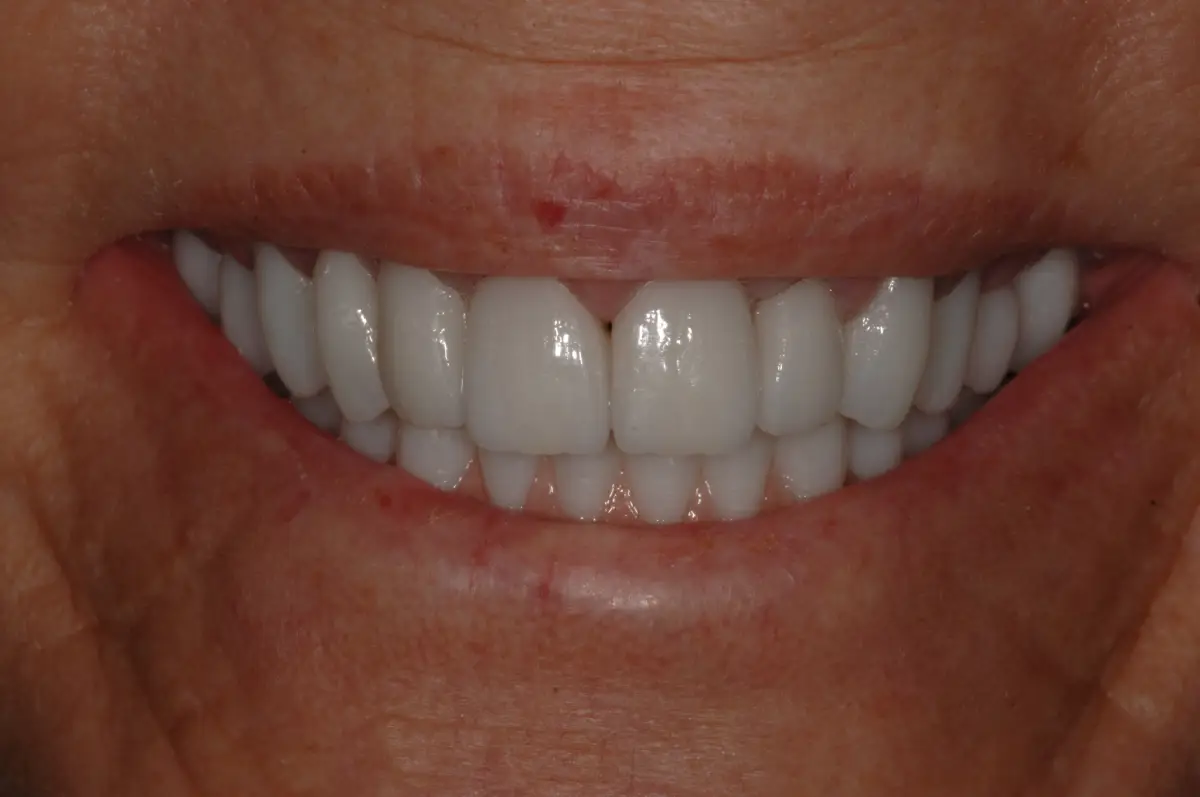

4D Full Mouth Rehabilitation

before

after